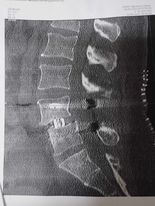

A délelőtt elég sűrűre sikerült. Tolószékben eltoltak a CT vizsgálatra. Az még érdekes megmozdulás volt, mert a székből is fel kellett állni, és le kellett feküdni arra a keskeny vizsgáló szalagra a hátamban a csővel. Rendkívül segítőkész volt a kis radiológus, köszönet érte. Az osztályra visszaérve jött a gyógyászati segédeszközös fiúka, aki levette a méreteimet és adott egy derékmerevítőt, valamint egy háttámaszt, amit széken ülve vagy autóban tudok használni. Ezek alanyi jogon jártak, ingyen és bérmentve. (Meglepődtem, mert tavaly a nyakmerevítőért, ami sokkal egyszerűbb valami volt fizetnem kellett.) Egy hónapig ezekben lehetett léteznem. Mivel a hátam már stabilizálva lett jöhettek a gyógytornászok. Elláttak jó tanácsokkal, hogyan feküdjek, hogyan üljek, mennyi ideig lehetek autóban stb.. Mutattak néhány hasznos tornagyakorlatot és sétáltunk is egyet. Azt ígérték, másnap már lépcsőzni is fogunk.

És délután fél 1-kor meglepetéssel érkezett a doktornő. Hozta a zárójelentésemet, a beutalókat a következő ellenőrzésekre, az előző nap készült felvételeket a gerincemről. Elmondta, hogy tényleg minden rendben van, mehetek haza! Azt se tudtam hirtelen kinek telefonáljak, hogy jöjjön értem, de rettenetesen boldog voltam. A férjem elindult haza a munkahelyéről, és 48 órával a műtétem után már úton voltam az otthonom felé.

Az eljárás neve: TLIF ágyéki gerincstabilizáció. Nem sérv, vagy porckorong műtét, hanem az instabil gerinc helyreállítása. Akkor van rá szükség, ha 2 csigolya kapcsolata nem teljesen stabil, ha csigolyacsúszás áll fenn. Ennek következtében az ágyéki csigolyák között a kapcsolatot biztosító porckorongok, kisízületek és a szalagrendszer meggyengülnek vagy károsodnak. Nekem az L4-L5-ös csigolyáim között már nem volt porckorong, egymáson ültek, így a gerinccsatorna, valamint a gyökcsatornák beszűkültek, nem volt átjárható "lyuk" közöttük, így az ideggyökök beszorultak, illetve a gerincvelő végéből származó rostoknál funkciózavar lépett fel. Továbbá az L4-es csigolya 1 cm-re elcsúszott a hasfalam felé.

A csigolyák közötti hiányzó porckorong helyére egy távtartót ékeltek be, ami 8 mm-re felemelte a felső csigolyát. Ez nem a legoptimálisabb távolság, mert az egészséges csigolyáim között 12 mm a rés, de ennél többet nem lehetett emelni rajta.

Valamint az érintett csigolyákba hátulról csavarokat vezettek be, s ezeket rudakkal kötötték össze. A visszahúzás sem tökéletes, annyira csúszott a helyére az L4-es csigolyám, amennyire tudott. Szóval most 6 csavar tartja stabilan az ágyéki gerincem eldeformálódott részeit.